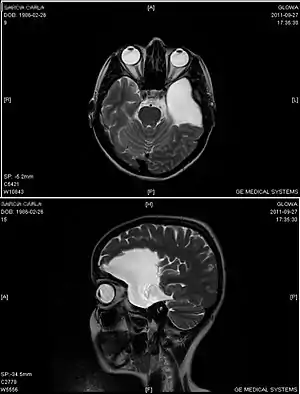

An MRI of a 25-year-old woman with left frontotemporal arachnoid cyst.